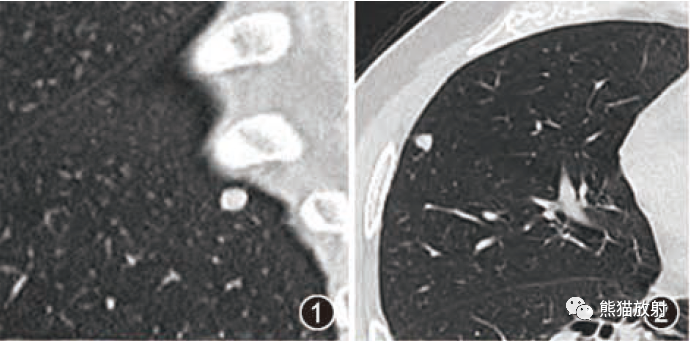

张力性纵隔气肿影像表现及严重度分级  迅速增大的肺部结节,首先考虑良性,确诊需要肺穿

迅速增大的肺部结节,首先考虑良性,确诊需要肺穿  肺隔离症:易误诊为肺癌的占位性病变,肺穿刺禁忌!